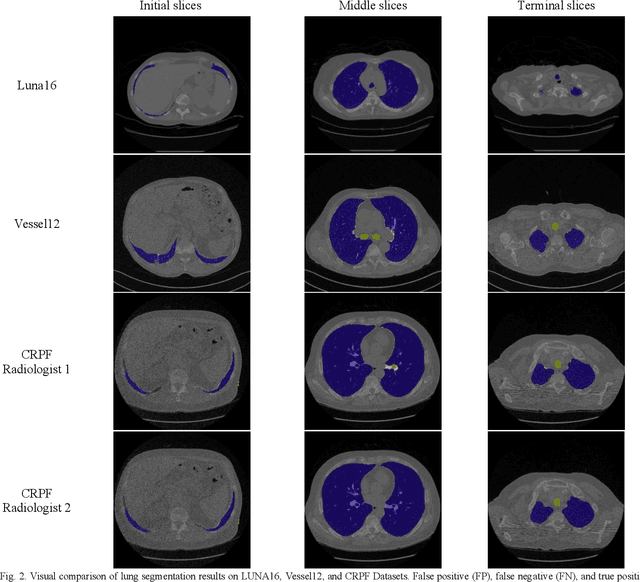

Segmentation of lung tissue in computed tomography (CT) images is a precursor to most pulmonary image analysis applications. Semantic segmentation methods using deep learning have exhibited top-tier performance in recent years. This paper presents a fully automatic method for identifying the lungs in three-dimensional (3D) pulmonary CT images, which we call it Lung-Net. We conjectured that a significant deeper network with inceptionV3 units can achieve a better feature representation of lung CT images without increasing the model complexity in terms of the number of trainable parameters. The method has three main advantages. First, a U-Net architecture with InceptionV3 blocks is developed to resolve the problem of performance degradation and parameter overload. Then, using information from consecutive slices, a new data structure is created to increase generalization potential, allowing more discriminating features to be extracted by making data representation as efficient as possible. Finally, the robustness of the proposed segmentation framework was quantitatively assessed using one public database to train and test the model (LUNA16) and two public databases (ISBI VESSEL12 challenge and CRPF dataset) only for testing the model; each database consists of 700, 23, and 40 CT images, respectively, that were acquired with a different scanner and protocol. Based on the experimental results, the proposed method achieved competitive results over the existing techniques with Dice coefficient of 99.7, 99.1, and 98.8 for LUNA16, VESSEL12, and CRPF datasets, respectively. For segmenting lung tissue in CT images, the proposed model is efficient in terms of time and parameters and outperforms other state-of-the-art methods. Additionally, this model is publicly accessible via a graphical user interface.